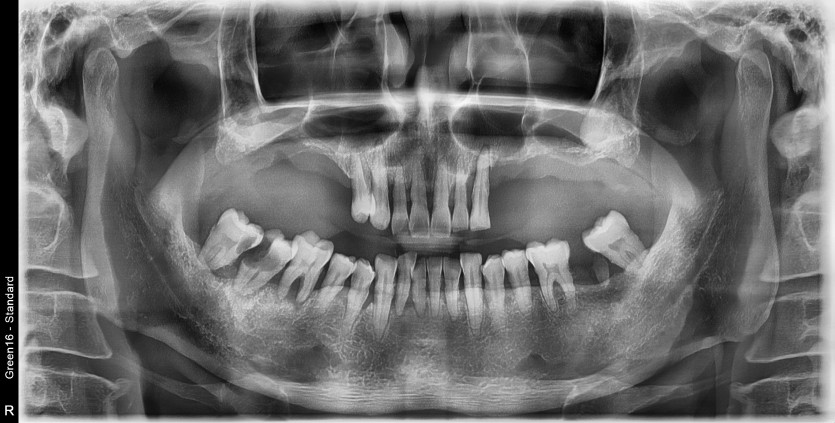

전체 임플란트 증례입니다.

18개의 임플란트로 완성하였습니다